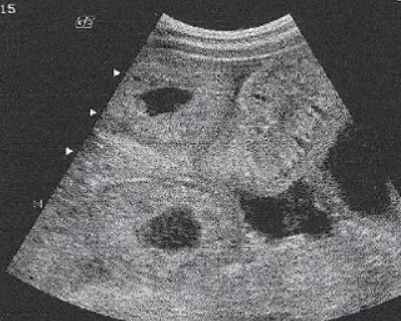

Acute appendicitis